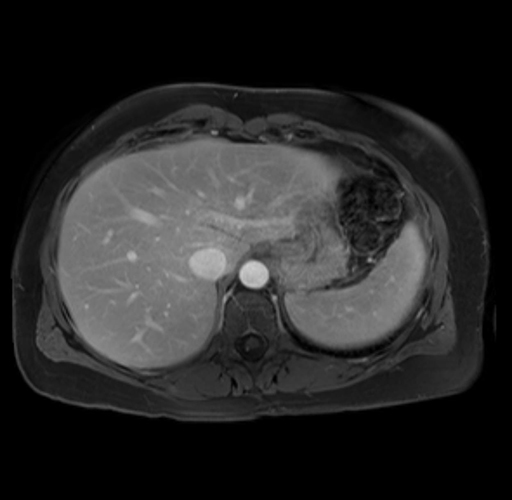

Imaging Analysis

Look through the patient's CT scan to identify any areas of concern for the necessary procedure.

Based on your CT findings, which issue(s) are present and would give reason for "planned slowing down moment(s)" in this case?

Considering a standard distal pancreatectomy procedure, what step(s) of the operation would you do differently in this case?